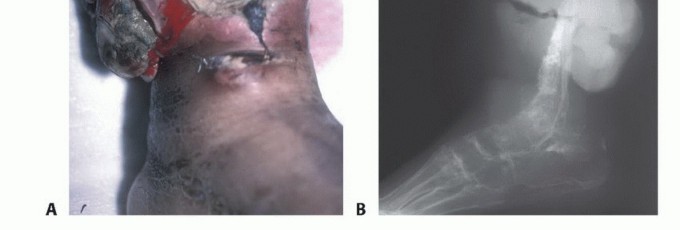

Clinical & Radiographic Imaging